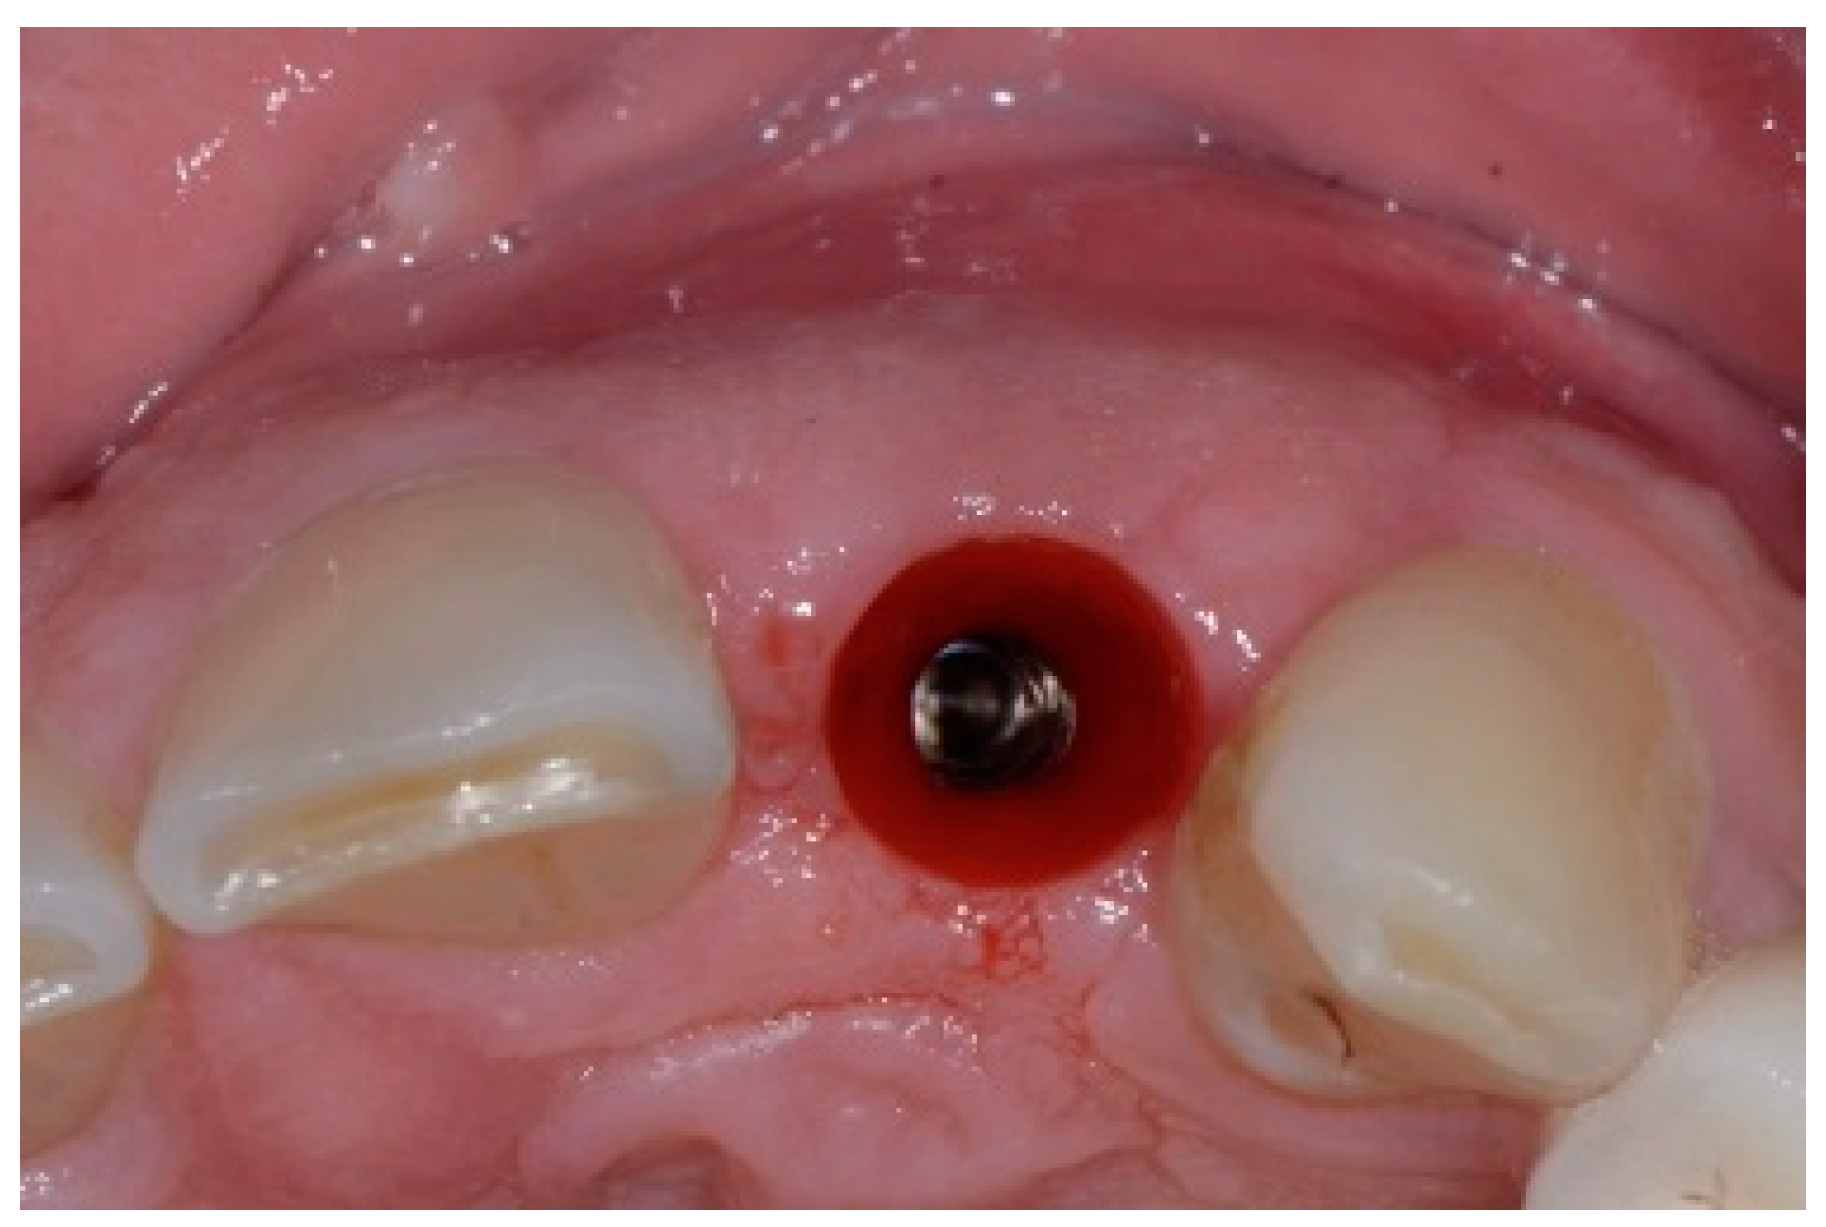

A 50-year-old female in good health and a non-smoker presented to our clinic with a failing maxillary left central incisor (Figure 13). The treatment plan consisted of the extraction of the existing tooth and replacing it with an implant. The preoperative surgical protocol described in patient 1 was followed. An L-shaped aesthetic flap design was used, revealing a buccal wall defect (Figure 14). The implant was placed with a screw-retained chair-side temporary crown (Figure 15), followed by the placement of bone graft material over the boney defect (Figure 16). A double-layer collagen membrane was placed and the flap closed. After six months, the final ceramic crown was inserted (Figure 17).

Figure 13.

Clinical view of extraction site (note tissue above tooth #9).

Figure 14.

Clinical view of extraction site implant.